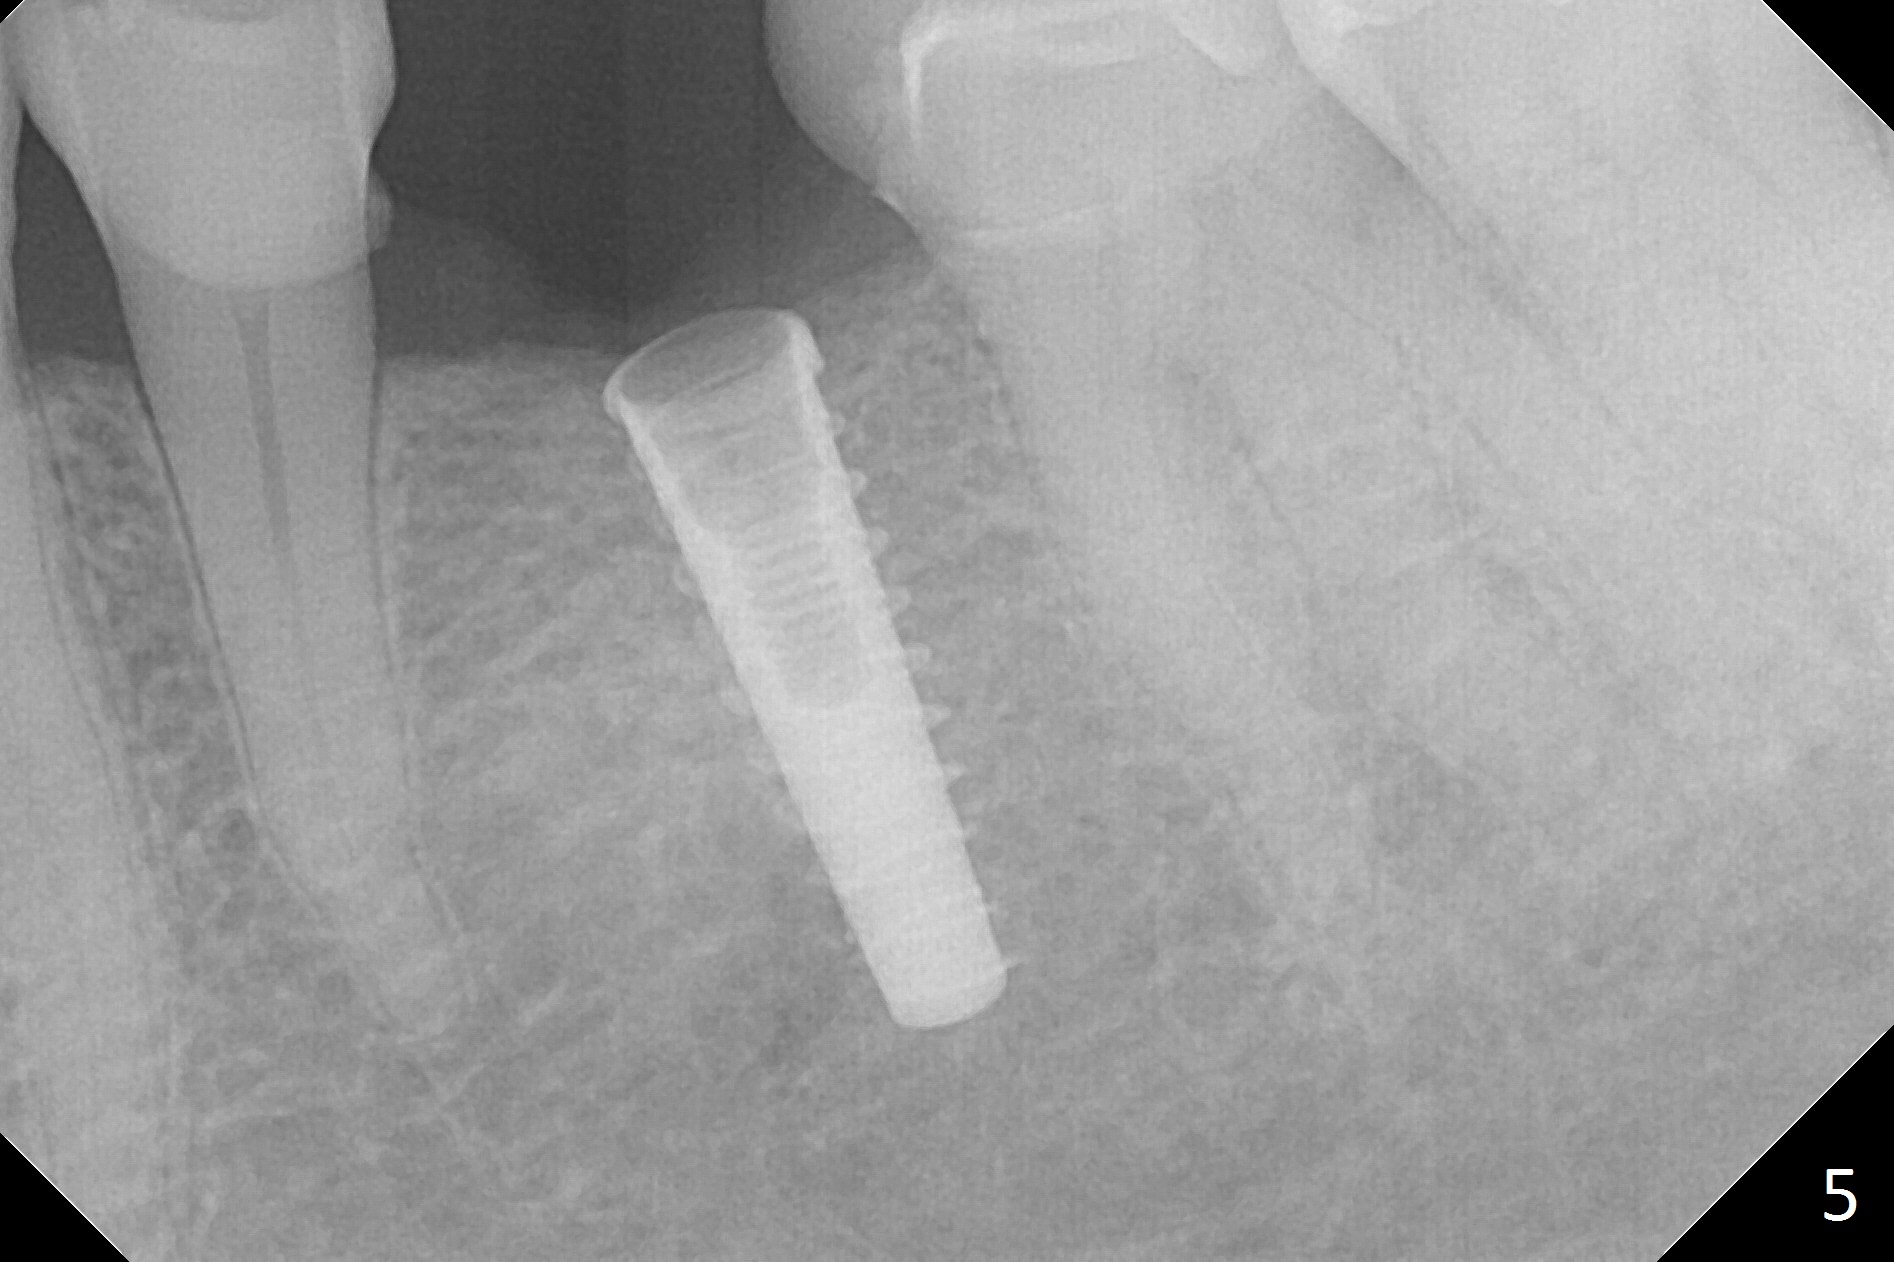

Initial osteotomy with 1.6 mm drill for 11 mm seems to be distal (Fig.1). The trajectory should be changed as shown by the black line in Fig.2; the drawback would be close to the Mental Loop (red line). Fortunately the trajectory is changed, but not so much as to be close the Loop when a 4x11 mm dummy implant is placed (Fig.3). When a 4x13 mm IBS is placed with 46 Ncm, there is clearance from the Loop (Fig.4-6). In fact there is no postop paresthesia. The main point is no block anesthesia. Infiltration anesthesia is administered with 34 mg Xylocaine with 17 mcg Epinephrine. The patient experiences dull pain when the implant is placed (Fig.4-6). After further anesthesia with 68 mg Septocaine, 17 mcg Epinephrine, the implant is torqued for a few turns (still with some discomfort). Finally autogenous bone with Osteogen is placed around the implant following placement of a 4.5x4(2) mm abutment. To reduce anxiety, a shorter implant should have been used. The patient complains of cold sensitivity in the lower left quadrant 4 months postop (Fig.7): the implant apparently close to the Mental Loop. Without an immediate provisional, the gingiva around the abutment is healthy.